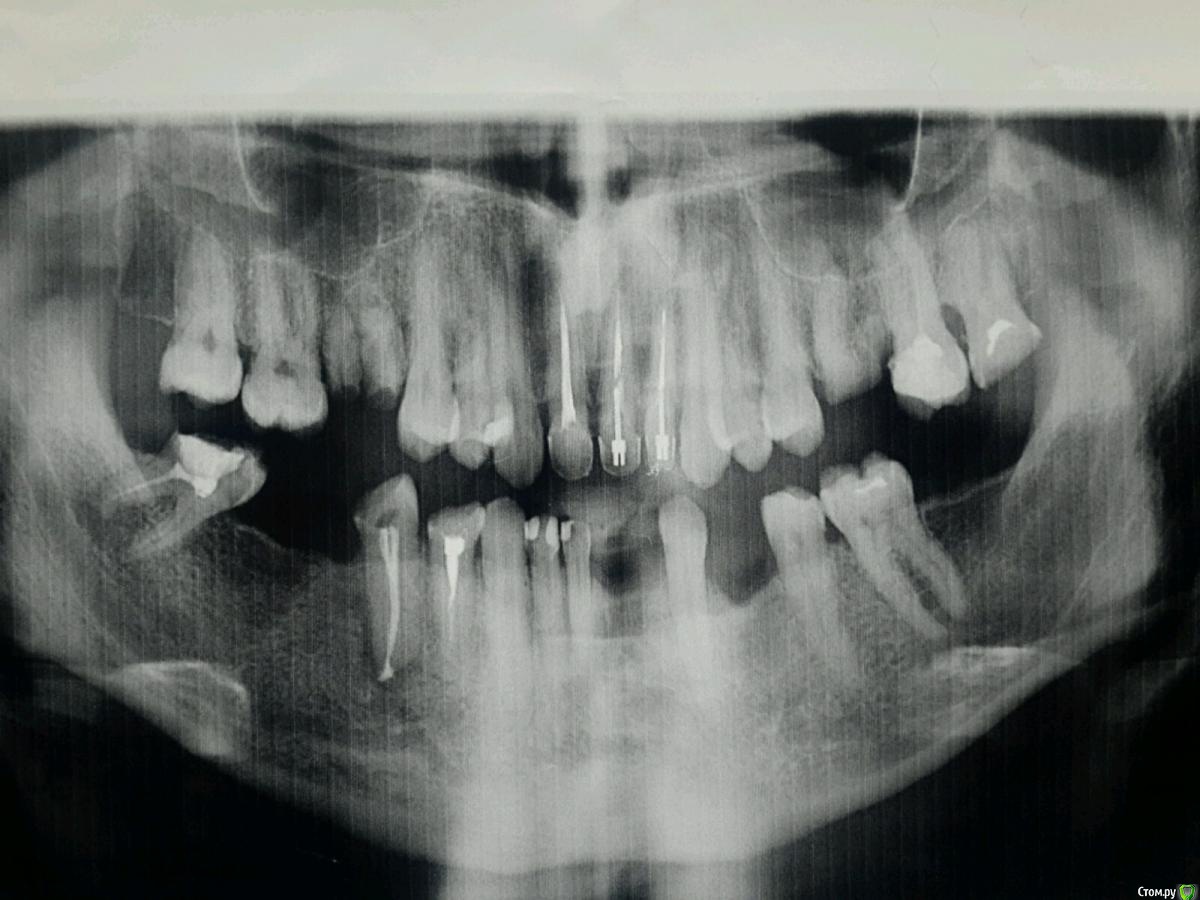

DIMTO Опубликовано 21 октября, 2015 Поделиться Опубликовано 21 октября, 2015 СКАЖИТЕ ПОЖАЛУЙСТА КАКОЙ СЪЕМНЫЙ ПРОТЕЗ ЛУЧШЕ В ЭТОМ СЛУЧАЕ ПРИМЕНИТЬ? Ссылка на комментарий